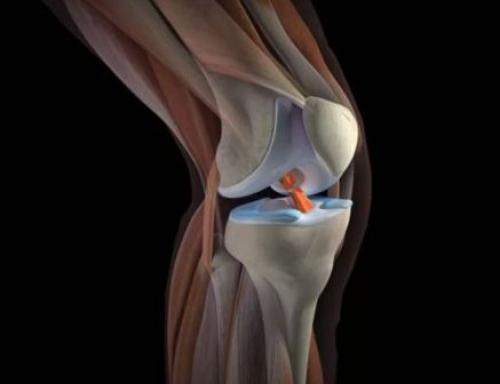

Чтобы лучше понять, почему болят колени, нужно разобраться с их анатомией. Итак, сочленение состоит из бедренной, большой берцовой кости и коленной чашечки. Две самые большие кости имеют по два выступа: внутренний и наружный мыщелки.

Все поверхности, которые соприкасаются друг с другом, покрыты гиалиновым хрящом. Благодаря ему обеспечивается подвижность коленного сустава, его амортизационные свойства. Вокруг этого соединения костей находится своеобразная капсула, изнутри выстланная синовиальным слоем. Она наполнена, благодаря которой производится питание сочленения, обеспечивается его подвижность.

Коленный сустав состоит не только из костей. Все его элементы объединяются крестообразными и коллатеральными связками, бедренными мышцами, сухожилиями. Коленная чашечка крепится к другим элементам посредством собственной связки. Для того чтобы колено двигалось, необходимо 6 синовиальных сумок. Питание и иннервация представленного сустава осуществляется посредством нервов и кровеносных сосудов, которые размещены в мягких тканях, окружающих сустав.

Колено соединяет бедро и голень. В составе коленного сустава:

- Надколенник или коленная чашечка, расположенная спереди,

- Две крупные кости – бедренная и большеберцовая, именно их соединяет колено,

- Хрящевая прокладка – мениск, уменьшающая силу трения между этими двумя костями и обеспечивающая полноту движений в суставе,

- Суставные сумки с синовиальной мембраной, ответственной за обмен веществ, и внутрисуставной жидкостью.

Менисков в колене – два, соответственно поверхностям: внутренний и наружный. Внутренний, плотно спаянный с капсулой, занимает приблизительно 60 % поверхности большеберцовой кости. Наружный – толще и шире. Форма внутреннего – в виде буквы С, а наружного – округлая, как несомкнутое кольцо. Кроме этого, в колене – большой аппарат мышц и связок.

Оба мениска состоят из коллагеновых волокон, находящихся в тесном переплетении и расходящихся в различных направлениях. Эти волокна образуют очень прочную на разрыв ткань. И сдвинуть ее тоже очень сложно.

Небольшое количество ткани мениска (0, 6 %) приходится на эластин, который, естественно, делает ткань эластичной – после любой деформации мениск быстро восстанавливает свою форму, являясь отличным амортизирующим средством.

С возрастом количество как коллагена, так и эластина в суставе снижается, что приводит к его дегенерации и уменьшению упругости хряща.